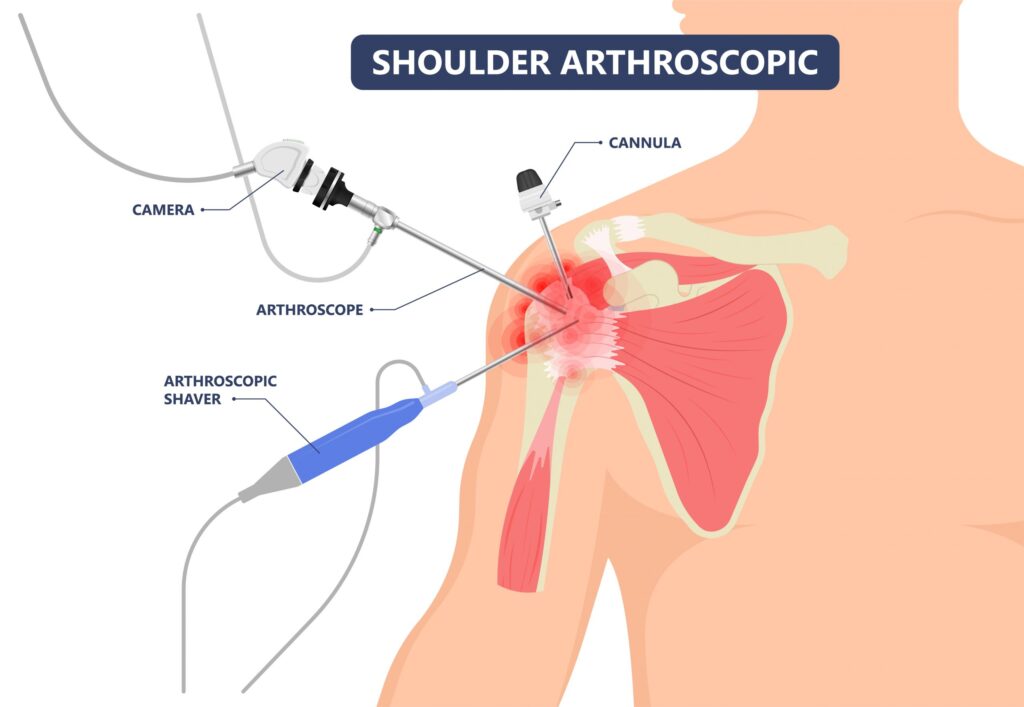

Shoulder Arthroscopy

Shoulder Arthroscopy

Shoulder injuries often occur due to repetitive overhead activities, falls, or trauma. Conditions such as rotator cuff tears and shoulder instability can severely limit arm movement and cause persistent pain.

Shoulder arthroscopy helps treat:

Rotator cuff repair

Bankart repair (shoulder instability)

Labral tears

Frozen shoulder

Impingement syndrome

Because the procedure is minimally invasive, patients experience less discomfort and regain mobility faster compared to traditional surgery.